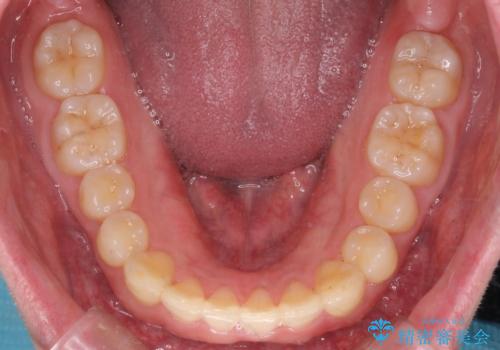

下の歯のがたつきが気になる。 インビザラン&ワイヤー部分矯正併用

- 下の歯が気になるとの事で来院。

左上の奥歯がシザーバイトがありワイヤーで部分的な矯正を行い、シザーバイトを改善した後にインビザラインで全体的な矯正治療を行いました。

歯のがたつきが改善され大変満足されました。